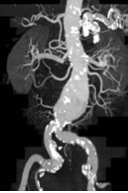

Abbildung 1a,b: CTA und MRA bei Nierenarterien-Stenose

Abbildung 3a,b: Junge Frau mit Bluthochdruck – Nierenarterien-Stenose rechts (FMD) vor und nach PTA

Abbildung 4a,b: Älterer Herr mit eingeschränkter Nierenfunktion, Bluthochdruck und Aortenaneurysma. CTA und Angiographie mit Nierenarterien-Stenose links.

Abbildung 5a,b: Derselbe Patient wie Abb. 4. Das Aneurysma wurde mit einem Stentgraft behandelt. MRA Kontrolle des Stentgrafts mit Darstellung der Nierenarterien-Stenose links.

Abbildung 6a,b: Während und nach Stent-Implantation bei demselben Patienten.

Abbildung 7a,b: Patientin mit Bluthochdruck (160/110 mmHg unter Therapie) – beidseitige Nierenarterien-Stenose – vor und nach Stent.